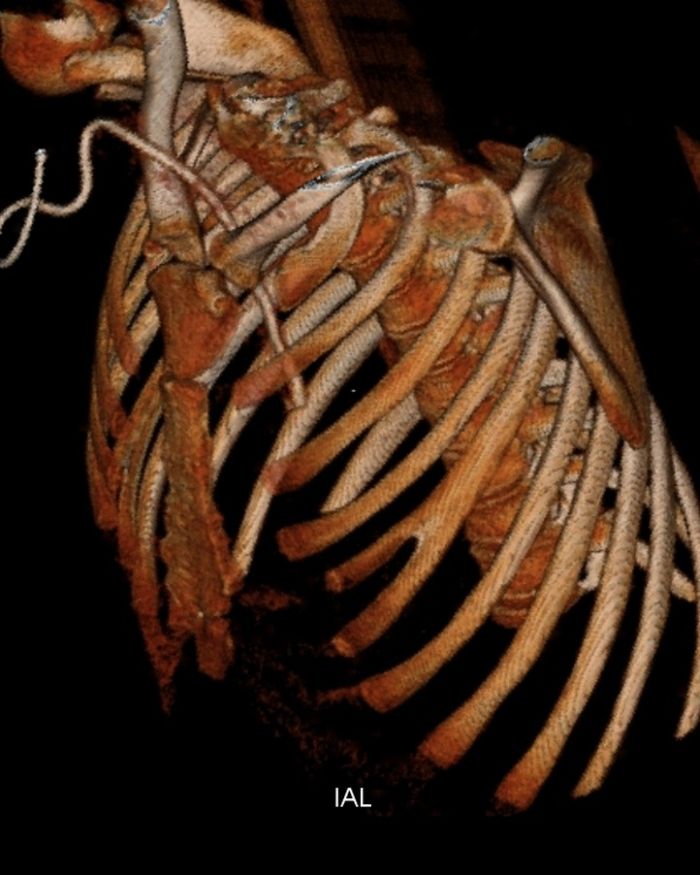

Bifid rib Radiology Cases

from radiologycases.my